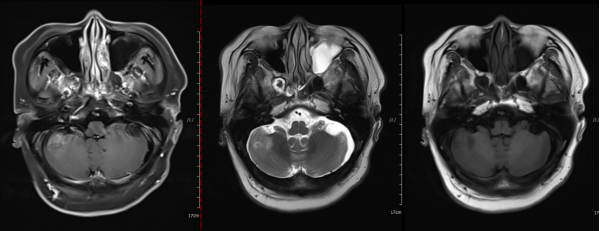

Figure 2: Comparison of the left basal ganglia and left temporal lobe before and after treatment. Irregular isointense T1 and mixed slightly long T2 signal shadows are visible in the left basal ganglia and left temporal lobe, surrounded by extensive edema signals, with no enhancement on contrast scan. There is localized absence of the frontal, temporal, and parietal bones. Abnormal signals in the left basal ganglia and left temporal lobe show a reduction in lesion extent and decreased enhancement compared to the pre-treatment condition.